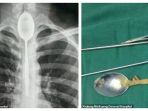

Pria Tiongkok ini Hidup dengan Sendok Logam Berukuran 8 Inci di Kerongkongannya Selama Setahun

Seorang pria Tiongkok menelan sendok logam berukuran 8 inci dalam aksi bodohnya setahun lalu.